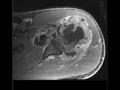

Giant Cell Tumor Humerus

53-year-old female who presents for chronic left shoulder pain. There is an infiltrative proton density isointense, STIR hyperintense, diffusion restricting and heterogeneously enhancing mass involving the proximal left humerus. There is a complex left shoulder effusion with heterogeneous enhancement. The tumor extends to the proximal left humeral epiphysis. Differential diagnosis includes giant cell tumor, chondroblastoma, chondromyxoid fibroma, metastatic disease and plasmacytoma. On biopsy, this was found to be a giant cell tumor. Giant cell tumors are relatively common benign tumors which are found arising from the metaphyseal regions with extension to the physis of long bones. The peak between 20-30 years of age with a slight female predilection. Presentation is usually insidious and related bone pain, soft tissue mass, compression of surrounding structures and possibly pathologic fracture. Lesions more commonly occur in the distal femur, proximal tibia, distal radius, sacrum and vertebral bodies. Treatment is with curettage and packing.